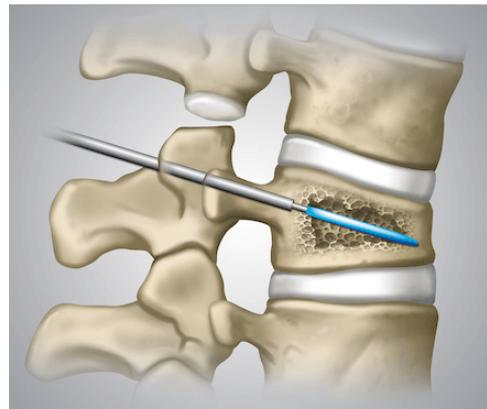

- Kyphoplasty: Reserved for patients with recalcitrant symptoms after 4-6 weeks of nonoperative treatment